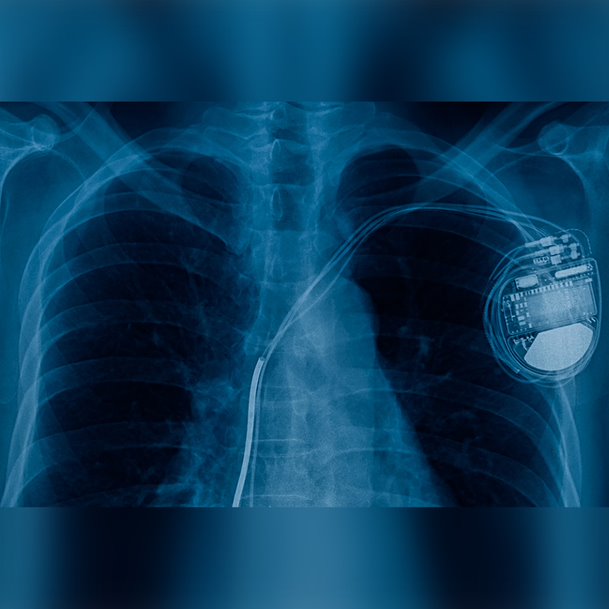

These are pacemakers and defibrillators that are placed using a special “third” lead place behind the major pumping chamber (left ventricle) of the heart. This technology has been shown to improve the function of this chamber in the majority of patients in whom they are implanted.